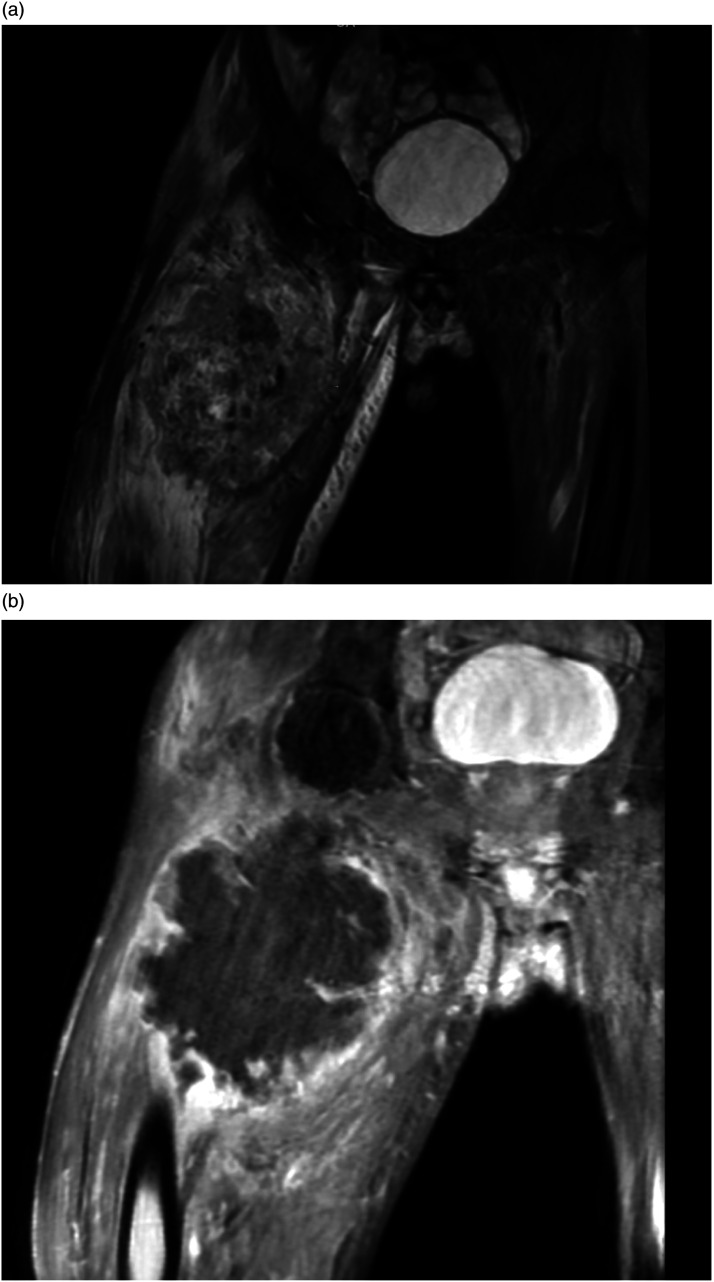

Cardiac metastases are the most frequent cardiac tumors. They can cause dysrhythmia, myocardial dysfunction, pericardial effusion, and heart failure. In decreasing order, the major primary malignancies associated with cardiac metastases are pleural mesothelioma, lung adenocarcinoma, undifferentiated carcinomas, lung squamous cell carcinoma, and breast carcinoma. Cardiac metastasis of sarcomas is uncommon, and only a limited number of cases have been found in literature. We report the case of an incidentally discovered cardiac metastasis when assessing the extension of a thigh mass in a 45-year-old man.

Abstract Image